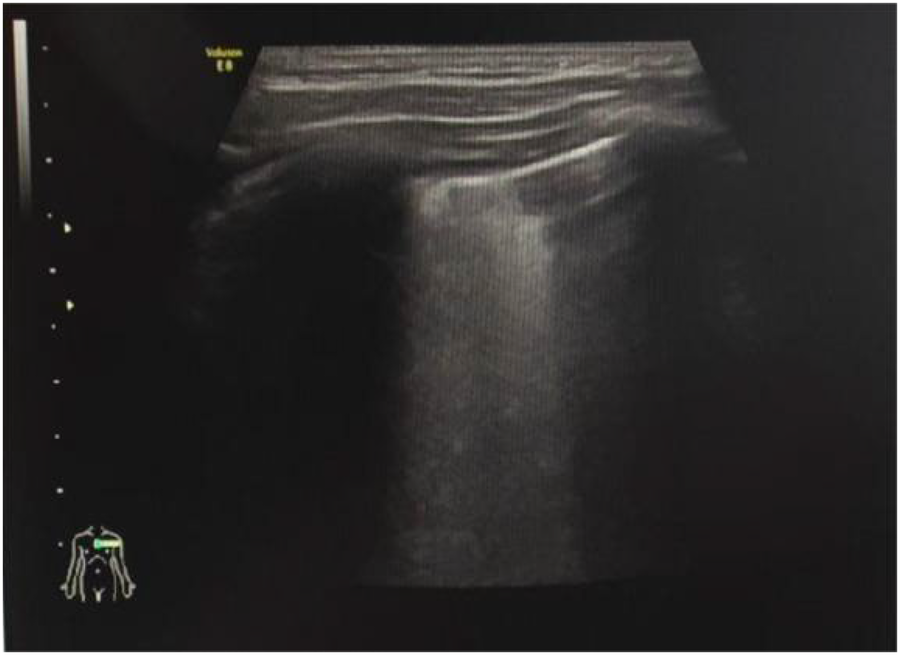

Observation Group 2: diffuse B-lines (Figure 3).

Observation Group 3: multiple B-lines (defined as ≥3 B-lines in any intercostal space).

Observation Group 4: few B-lines (defined as <3 B-lines in any intercostal space).

Figure 3. B-line (patient 2).